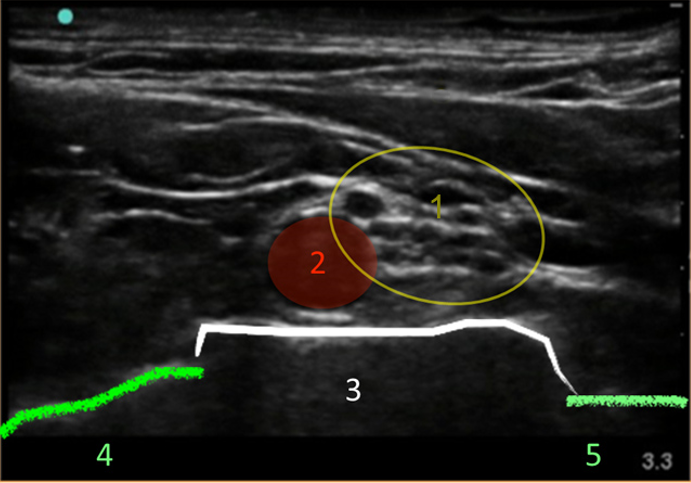

Supraclavicular Ultrasound Technique Image

Brachial Plexus

Artery

1st Rib

Pleura